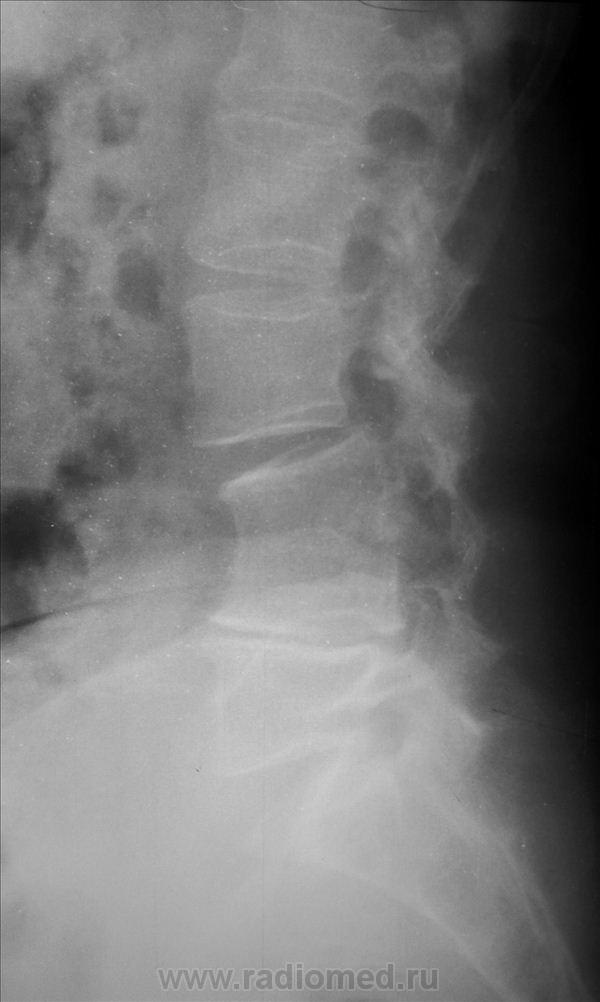

Добрый вечер, Александр Викторович.Интересно, это впервые выявленная находка или есть архив, анамнез?Жаль, остистые отростки не очень хорошо визуализируются-может быть, они тоже сращены.Может и нет.При врожденной конкресценции остистые отростки сращены.Здесь же локальный кифоз на уровне 3-4 позвонков, клиновидность тел, выраженное снижение высоты межпозвонковых дисков выше- и нижележащих.Больше данных за посттуберкулезнвй спондилит, вернее его последствия, хотя не факт, травма тоже могла так обезобразить позвоночник.Если можно, уточните анамнез, пожалуйста.

Вот и снимки

Диф. диагностика с посттравматическим и посттуберкулезным костным блоком. Дуги не сращены, насколько я смогла рассмотреть.

Конкресценция (врожденная). Отсутствие намека на реактивный остеосклероз, однородность костной структуры, указывают против инфекционного процесса.

Для врожденного смущает структура в задних отделах.

+ укорочение и деформация ножек дужек.